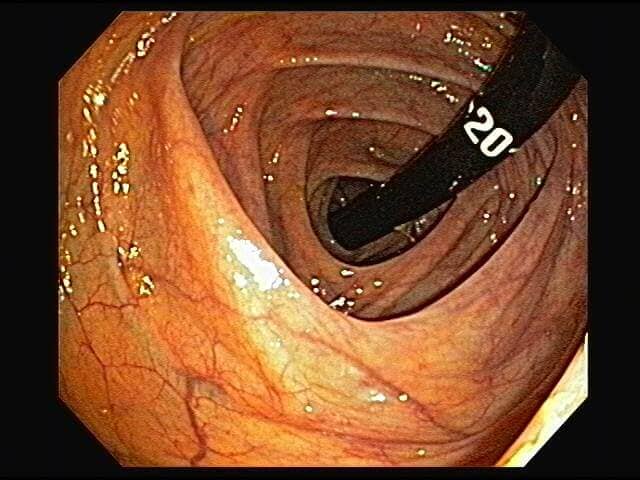

ENDOSCOPIA DIAGNÓSTICA Y TERAPÉUTICA AVANZADA CON ALTA DEFINICIÓN

⚕ Endoscopia de alta definición

⚕ Videoendoscopia y biopsias

⚕ Videocolonoscopia